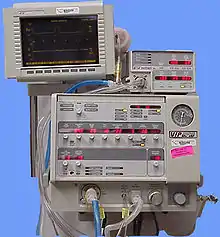

- Airway access for prolonged mechanical ventilation

In the chronic (long-term) setting, indications for tracheotomy include the need for long-term mechanical ventilation and tracheal toilet (e.g., comatose patients, extensive surgery involving the head and neck). Tracheotomy may result in a significant reduction in the administration of sedatives and vasopressors, as well as the duration of stay in the intensive care unit (ICU).[4][5]

If prolonged ventilation is required, tracheostomy is usually considered. The timing of this procedure is dependent on the clinical situation and an individual's preference. An international multicenter study in 2000 determined that the median time between starting mechanical ventilation and receiving a tracheostomy was 11 days.[6] Although the definition varies depending on hospital and provider, early tracheostomy can be considered to be less than 10 days (2 to 14 days) and late tracheostomy to be 10 days or more.

Biphasic cuirass ventilation is a form of non-invasive mechanical ventilation that can — in a small subset of cases — allow people to avoid a tracheostomy.[7]